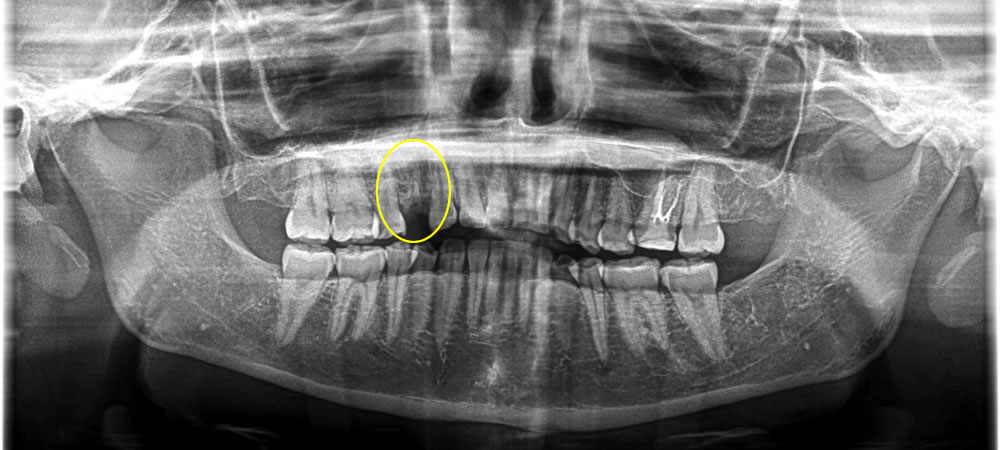

保存不可能な歯を抜歯後にインプラント治療を実施した症例

こちらの患者さまは、右上の第一小臼歯のむし歯を放置してしまい、笑った時の見た目が気になるとのことで来院されました。

むし歯により歯の頭は無くなり、レントゲン上では根っこが残っていることが確認できましたが、放置していた期間が長すぎたため、歯茎がかぶってしまい歯を残すことができないという診断になり、抜歯をすることになりました。